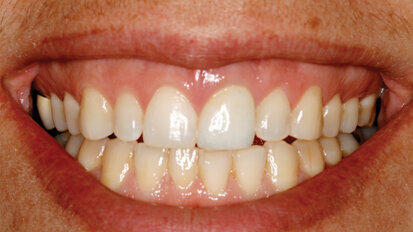

Lepljenje fragmenta i nadogradnja frakturiranog maksilarnog centralnog sekutića

Akutna dentalna trauma je veoma česta među decom mlađom od 12 godina. Najčešće povređivani zubi su maksilarni sekutići, a prilikom traume ...